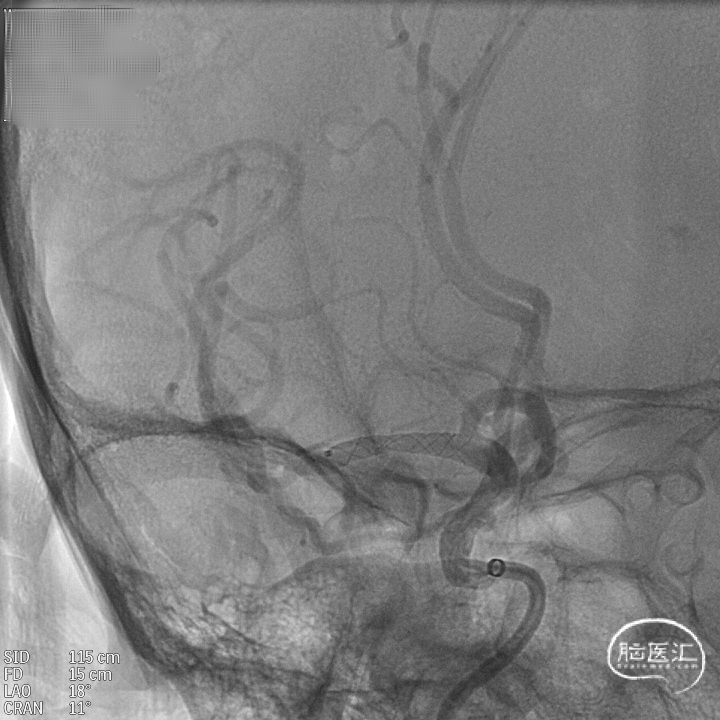

DSA:DSA提示右侧颈内动脉C6段可见多发动脉瘤。

其他血管造影未见明显异常。

术前诊断:右侧颈内动脉C6段多发动脉瘤。

治疗方案:血流导向装置植入术。

载瘤动脉远端血管直径:4.0mm

载瘤动脉近端血管直径:4.9mm、4.5mm(两个角度)

支架到位,远端打开(正侧位):4.75-20mm支架在大脑中动脉M1段打开,回撤至C6段远端锚定。支架释放过程中,轻柔推送支架系统,可见支架导管沿血管壁大弯侧走行,支架打开良好。